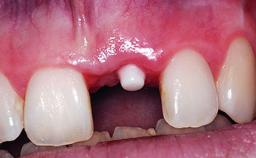

A 32-year-old female Caucasian patient with a compromised maxillary right central incisor was referred to us by a general dentist. Her chief complaints were discomfort and mobility of tooth 11 with unsatisfactory esthetics due to discoloration. The patient reported a previous trauma, some years earlier, as the origin of pathology on the afflicted tooth. Anamnesis was negative for any other dental or periodontal pathology in the remaining dentition. The patient did not take any medication and reported to be a light smoker (5–10 cigs/day). She had high esthetic expectations of her treatment. The extraoral examination revealed a high smile line with full exposure of her maxillary teeth and surrounding soft tissue in the area between the second premolars.

Defining Characteristics One missing tooth to be replaced by an implant-borne prosthesis

Placement Protocol Early or late implant placement

Bone Volume Deficient horizontally, requiring prior grafting